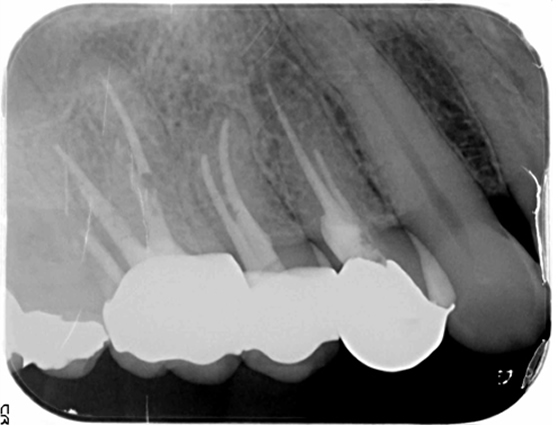

基本上,在没有症状或症状轻微的情况下,即使龋齿较大并且细菌已经到达牙神经,通常也不需要进行根管治疗,可以进行神经保存治疗(保存疗法)。

为此,需要进行准确的检查和诊断,以及使用适当的材料和器材进行治疗。